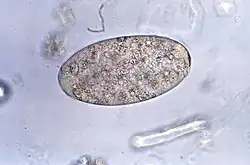

Rozpoznanie choroby stawiane jest na podstawie stwierdzenia jaj pasożyta (rzadziej dorosłych osobników) w kale (badanie koproskopowe) lub wymiocinach chorych. Jaja są elipsoidalne, z cienką błoną i zazwyczaj słabo zaznaczonym wieczkiem (operculum). Wielkość jaj waha się w granicach 130-159 na 78-98 µm. Nie jest możliwe rozróżnienie jaj Fasciolopis buski od motylicy wątrobowej[1].